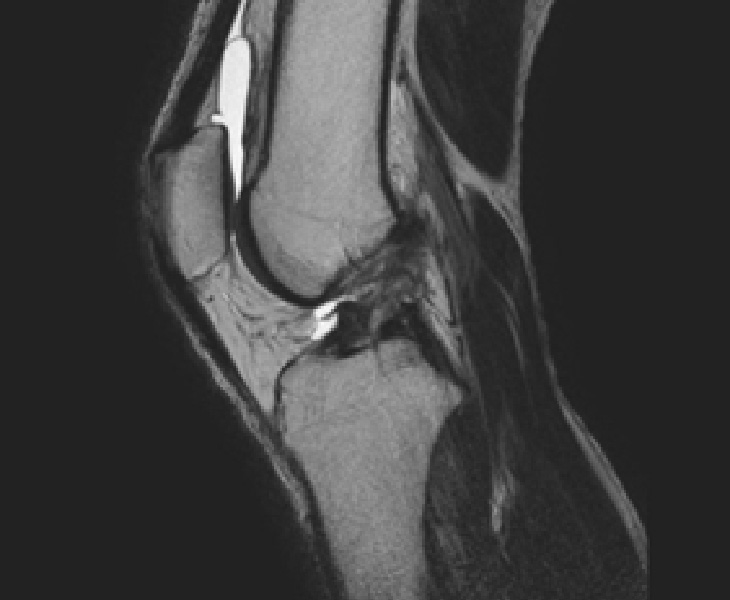

診察では膝の安定性を確認するテスト(前方引き出しテスト、ラックマンテストなど)を行い、MRI検査で靭帯の断裂の有無を確認します。

MRI・エコーなどの画像検査を組み合わせ、損傷の程度と機能を正確に評価します。